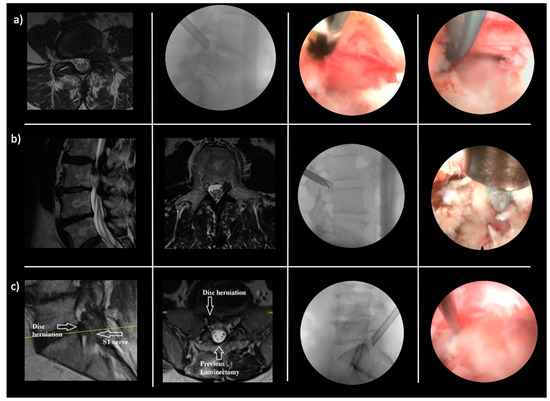

- Lewandrowski, K.-U.; Abraham, I.; León, J.F.R.; Telfeian, A.E.; Lorio, M.P.; Hellinger, S.; Knight, M.; De Carvalho, P.S.T.; Ramos, M.R.F.; Dowling, Á.; et al. A Proposed Personalized Spine Care Protocol (SpineScreen) to Treat Visualized Pain Generators: An Illustrative Study Comparing Clinical Outcomes and Postoperative Reoperations between Targeted Endoscopic Lumbar Decompression Surgery, Minimally Invasive TLIF and Open Laminectomy. J. Pers. Med. 2022, 12, 1065. [Google Scholar] [CrossRef]

- Yeung, A.; Roberts, A.; Zhu, L.; Qi, L.; Zhang, J.; Lewandrowski, K.-U. Treatment of Soft Tissue and Bony Spinal Stenosis by a Visualized Endoscopic Transforaminal Technique Under Local Anesthesia. Neurospine 2019, 16, 52–62. [Google Scholar] [CrossRef]

- Yeung, A.T.; Gore, S. In-vivo Endoscopic Visualization of Patho-anatomy in Symptomatic Degenerative Conditions of the Lumbar Spine II: Intradiscal, Foraminal, and Central Canal Decompression. Surg. Technol. Online 2011, 21. [Google Scholar]

- Lewandrowski, K.-U.; Yeung, A. Lumbar Endoscopic Bony and Soft Tissue Decompression With the Hybridized Inside-Out Approach: A Review And Technical Note. Neurospine 2020, 17, S34–S43. [Google Scholar] [CrossRef] [PubMed]

- Yeung, A.; Lewandrowski, K.-U. Early and staged endoscopic management of common pain generators in the spine. J. Spine Surg. 2020, 6, S1–S5. [Google Scholar] [CrossRef] [PubMed]